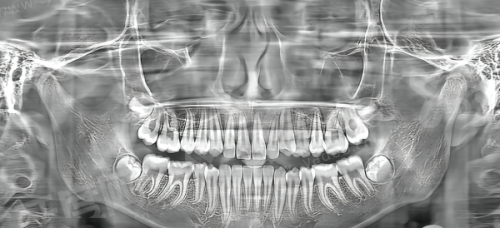

牙周炎治疗是莞大口腔的核心常规诊疗项目之一,能够开展龈上洁治、龈下刮治、牙周翻瓣术等标准化的牙周序列治疗方案,可以根据患者牙周炎的不同重度程度,提供对应的治疗措施,覆盖了轻度、中度、重度牙周炎的诊疗需求。